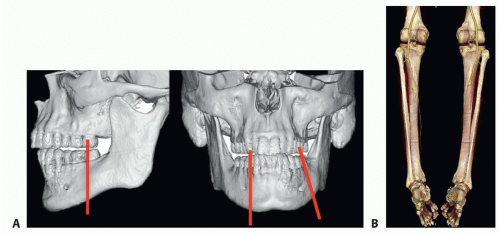

The mandible is a complex 3D structure with two symmetric points of articulation at the skull base forming the temporomandibular joint (FIG 1A).

The blood supply for the fibula is derived from the peroneal artery and vein (FIG 1B).

Fine cut (1-mm-thick sections) CT scans of the mandible and fibula with 3D reconstruction is the best option for examining the bone and for planning of the reconstruction. MR imaging may also be useful in some cases to evaluate the surrounding soft tissues but is not useful for developing 3D bone models (FIG 3).1,2

FIG 3 • A. Three-dimensional model of the mandible derived from thin cut CT scans demonstrating area to be resected (red bars). B. CT angiogram of the lower extremity and fibula anatomy.

Imaging of the fibula flap is typically done with a CT angiogram to evaluate the osseous anatomy as well as the vascular blood supply. The angiogram is used to evaluate the vascular anatomy of the lower extremity (three vessel runoff, abnormal vascular anatomy), and the perforator anatomy of the skin paddle. This imaging helps with planning the placement of the osteotomies and skin paddles.